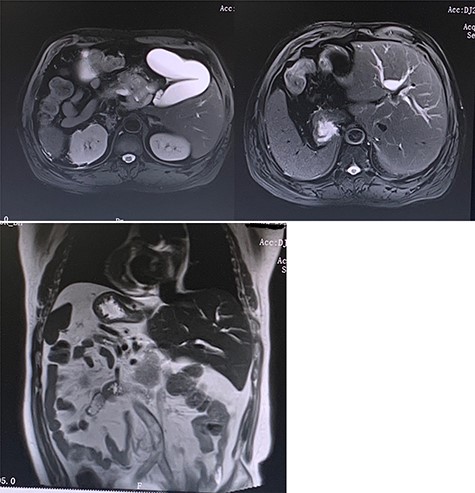

A 52-year-old male had no obvious inducement of epigastric pain for >3 months presenting persistent stabbing pain, accompanied by back pressure, fatigue, loss of appetite and hiccup. He went to a local hospital for treatment because of aggravated abdominal pain. Gastroscopy showed: (i) gastric polyps and (ii) chronic atrophic gastritis. The symptoms were not relieved after oral medication. Two weeks later he had jaundice with clay-like stool, so he went to the local hospital and underwent a color Doppler ultrasound examination. The results showed that: (i) visceral inversion; (ii) solid space-occupying at the head of the pancreas; (iii) dilated inner diameter of the intrahepatic and extrahepatic bile ducts and main pancreatic duct; (iv) fatty liver and (v) enlarged gallbladder volume and wall rough. The patient was admitted to our hospital complaining of ‘epigastric pain >3 months ago, jaundice with clay-like stool for 1 week’. The patient had no significant medical, surgical or drug history. Physical examinations were unremarkable except for a weight loss of ~20 kg since the onset of the disease. Blood and laboratory tests were carried out, and they showed elevated values of liver enzymes, with a clear elevation in the values of Enzyme gamma-glutamyl transferase (GGT) and alkaline phosphatase (ALP), as well as tumor markers CA19-9, CEA and CA72-4, which are indicative of the presence of an obstructive lesion (Table 1). After preoperative examinations, he was diagnosed with pancreatic cancer. His CT scan (Fig. 1) showed: (i) mirror dextrocardia; total visceral inversion; (ii) pancreatic space-occupying lesions; (iii) intrahepatic and extrahepatic bile duct dilation; (iv) intrahepatic calcification and (v) multiple small cysts in the left kidney, and the MRI scan has confirmed the previous results (Fig. 2). A perioperative plan has been made for a LPD. The patient was put under general anesthesia in a supine split–leg position. The laparoscopic instruments were connected (Fig. 3). Diagnostic laparoscopy confirmed a mirror transportation of organs hence confirming SIT, considering the preoperative assessments and intraoperative exploration, a LPD, and intestinal adhesiolysis was performed. Major vessels along with thoracic and abdominal organs were transposed as mirror images of the normal anatomy, a 17-cm paramedian incision in the upper left abdomen was made to accomplish the resection of the organs which includes the distal stomach—the duodenum, the upper segment of the jejunum, the common bile duct and the gallbladder. According to conventional loop reconstruction, the reconstruction of the alimentary tract was performed. Three drainage tubes were placed at the sites of the anastomoses. Although there were anatomical variations, the operation went smoothly. The blood pressure of the patient was stable and the anesthesia effect was satisfactory within 150-ml intraoperative blood loss. The postoperative specimens were sent to the pathological lab. Postoperative fluoroscopy was normal (Fig. 4). The patient had a total hospital stay of 26 days; 15 days postoperative hospital stay, and was discharged without any complications.

Preoperative MRI (T2 phase) confirming the SIT and showing the intrahepatic bile ducts dilation and the enlarged gallbladder with a space-occupying at the head of the pancreas.